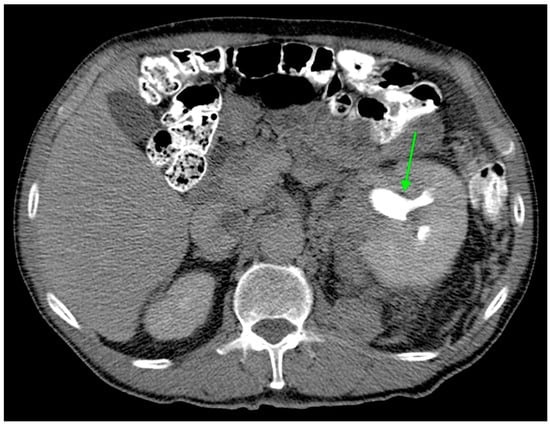

| Hydronephrosis | 6 (3.0%) | 4 (8.9%) | 2 (1.3%) | 0.025 |